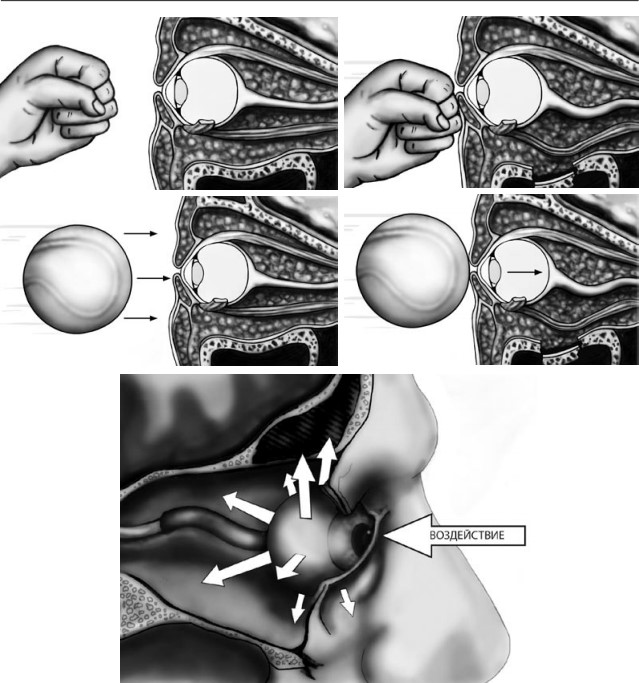

Любопытно, что, вопреки устоявшемуся мнению, удар теннисным мячом не приводит к пере-лому, хотя может вызвать повреждение глазного яблока. По-видимому, деформация полого мячика во время контакта и эффект присасывания, возникающий в момент отскока от периор-битальной области, демпфируетподъем внутриорбитального давления. Для возникновения перелома требуется воздействие неспособного к преходящей деформации ранящего агента, например, кулака.

При обширных оскольчатых дефектах нижней стенки мягкие ткани не столько ущемляются, сколько смещаются вниз под воздействием силы тяжести и реактивного отека. Не столь многочисленные сторонники «механической» гипотезы, сформулированной R. Le Fort (1901), считают основным механизмом взрывного растрескивания дна орбиты волнообразные деформации, передающиеся с подглазничного края.

В зависимости от направления вектора силы дно орбиты (в первую очередь его внутренняя половина) испытывает или горизонтальную, или ротаторную деформацию. Площадь перелома будет максимальной в случае, если ранящий агент движется снизу-вверх под углом 30º к подглазничному краю. Кинетическая энергия, требующаяся для разрушения дна глазницы путем волнообразной деформации и через гидравлический удар, практически одинакова, но локализация и протяженность «гидравлических» и «механических» переломов существенно различаются. Экспериментальные исследования на кадаверных орбитах продемонстрировали, что переломы, обусловленные волнообразной деформацией, ограничиваются передней половиной внутренней части дна глазницы, не распространяются на медиальную стенку и не сопровождаются ущемлением мягких тканей в зоне костного дефекта.

Гидравлический механизм вызывает гораздо более протяженные переломы, захватывающие не только всю нижнюю, но и медиальную стенку глазницы, пролапс мягких тканей и энофтальм. По мнению некоторых авторов, в возникновении перелома играют роль оба механизма, и противопоставлять их в корне неверно. Одновременная инициация обоих механизмов травмы, их сосуществование, взаимодополнение с доминированием в каждом конкретном случае какогото одного варианта и объясняет многообразие орбитальных фрактур.